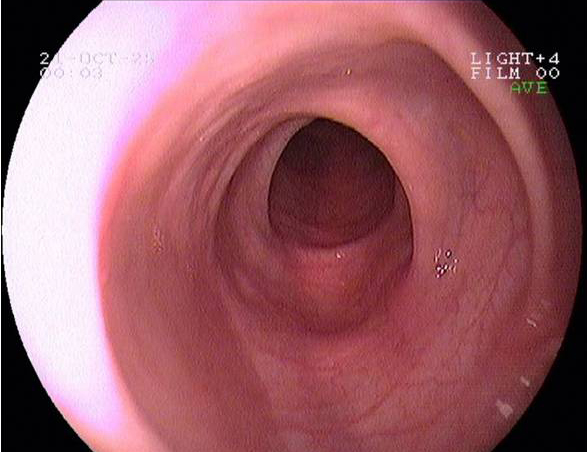

Imágenes tomadas durante la endoscopia digestiva alta y la colonoscopia. Se aprecia una mucosa de aspecto y vascularización normal, sin lesiones visibles. Se progresa con el colonoscopio hasta el íleon. Todo resulta macroscópicamente normal. Se toman biopsias de todos los segmentos explorados.

Pruebas complementarias: panendoscopia oral y colonoscopia

La endoscopia es el método de elección para el diagnóstico y seguimiento de la EII. Permite una visión macroscópica de la mucosa intestinal y la toma de múltiples biopsias para el estudio histológico.

En todos los pacientes en los que se sospeche una EII está indicada la realización de una colonoscopia completa con ileoscopia y una endoscopia digestiva alta.

Es la técnica de elección para diferenciar entre colitis ulcerosa (CU) y enfermedad de Crohn (EC), así como para localizar y valorar la extensión de la enfermedad.

Realizamos una endoscopia digestiva alta y una colonoscopia a la paciente con toma de biopsias, obteniendo el informe de Anatomía patológica.